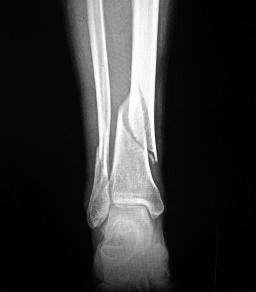

老王因为车祸致右小腿疼痛活动受限至A院就诊,急诊查看老王右小腿明显肿胀畸形,皮肤张力非常高,表面已冒出小水泡,万幸的是右足的感觉活动及血运未受明显影响。拍X线示右胫腓骨下段骨折,急诊给予石膏固定后收入病房。入院后几个小时,老王感到右小腿肿痛情况较前越来越严重,皮肤表面又冒出了几个水泡。医生与家属交代病情后建议老王行右跟骨结节骨牵引治疗来稳定骨折端,恢复下肢力线,来达到止痛及消肿的目的。签署知情同意书后牵引术顺利结束。几个小时过去了,老王发现他右小腿的肿痛症状未见明显好转,老王一家都很疑惑,不是说骨牵引后肿痛症状会明显缓解吗,为什么没有任何效果反而越来越严重了呢?后来仔细询问及查看牵引设备后医生找到了原因,由于牵引后只能平躺,不能翻身,老王又是个爱动的人,实在不能耐受,就私自移动了已经调整好的牵引方向,支架也移位了,导致设备的牵引作用大打折扣,达不到骨牵引预计的效果,还有可能起到了相反的作用。经过医生调整并向老王详细交代了注意事项,没多一会,老王的肿痛症状明显缓解,老王及家属吃下了一颗定心丸。

骨牵引,又称直接牵引,系利用钢针或牵引钳穿过骨质,使牵引力直接通过骨骼而抵达损伤部位,并起到复位、固定和休息的作用。其优点是可承受较大的牵引重量,阻力较小,可以有效地克服肌肉紧张,纠正骨折重叠或关节脱位所造成的畸形;牵引后便于检查患肢;牵引力可以适当增加,不致引起皮肤发生水泡、压迫性坏死或循环障碍;配合夹板固定,保持骨折端不移位的情况下,可以加强患肢功能锻炼,防止关节僵直、肌肉萎缩,以促进骨折愈合。缺点是钢针直接通过皮肤穿入骨质,若处理不当可引起针眼处感染;进针部位不准确,可损伤关节囊或神经血管;儿童采用骨牵引容易损伤骨骺。

常见肢体各部位骨骼牵引:颅骨牵引、尺骨鹰嘴牵引、股骨髁上牵引、胫骨结节牵引、跟骨牵引等。

2、牵引重量应根据患者年龄、体重、肌肉发达情况、骨折部位、移位程度,结合X线检查来决定。一般股骨牵引重量相当于体重的1/7-1/10,胫骨、跟骨牵引重量一般不超过5kg,老弱及骨质疏松患者应适当减轻牵引重量。对骨折或脱位患者,牵引重量应一次加到适当最大量。一旦复位后,即应将重量减至维持重量,牵引的最初几天,每日应测量肢体长度,检查骨折复位情况,并随时调整牵引重量,以防过度牵引。